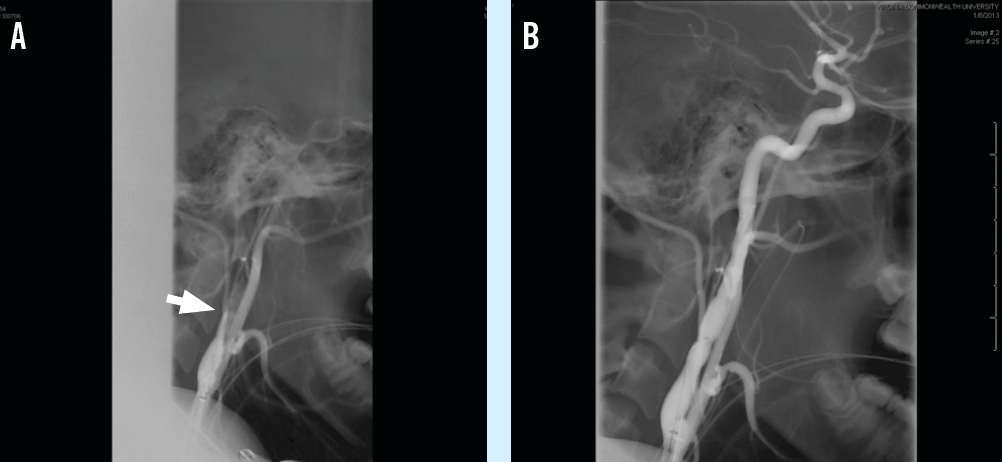

Jessica Serrano, MD; Clifton C. Lee, MD

A previously healthy 15-year-old boy presented to the emergency department (ED) after collapsing and having developed right-sided weakness.